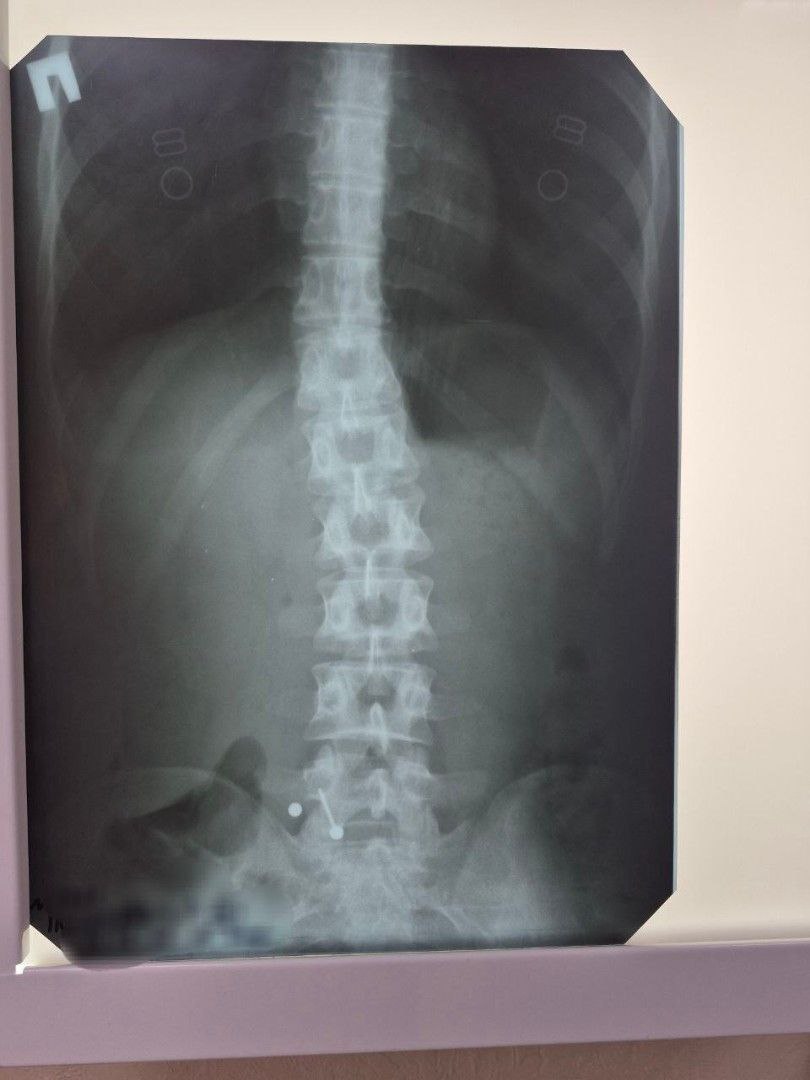

В Балаковскую горбольницу обратилась 20-летняя девушка. Она случайно проглотила украшение для пирсинга языка — металлическую «штангу» с шариком во время еды.

К врачам девушка обратилась не сразу. К тому времени инородный предмет уже переместился в тонкий кишечник, и безопасно извлечь его с помощью эндоскопа стало невозможно. Теперь, вероятно, пирсингу придётся выходить «естественным» путём.

А другая история: на той же неделе в больницу доставили 2-летнего малыша, проглотившего саморез. Благодаря оперативности мамы, врачи смогли быстро и безопасно извлечь опасный предмет.